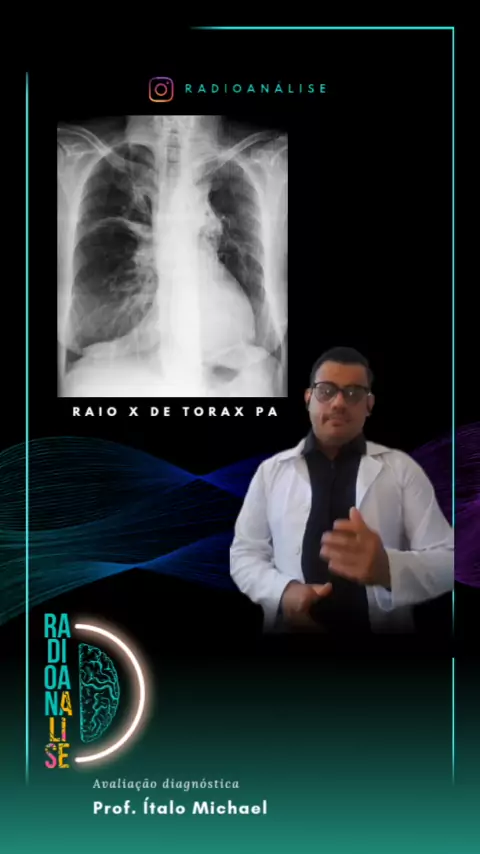

tudo bem? Eu me chamo Ítalo Michael sou técnico em radiologia,E hoje vamos falar um pouquinho sobre raio-x do tórax e também falar sobre anatomia radiológica e patologia apresentada na imagem,mas Lembrando que quem fecha o diagnóstico são os médicos não sou eu técnico e nem os tecnólogos em radiologia o meu intuito é te ensinar a interpretar este tipo de imagem em radiologia. TR° Ítalo Michael CRTR -07244t #raiox #anatomia #radiologia #medicinaporamor #viral

raio x de torax #med #T_Enfermagem #radiology